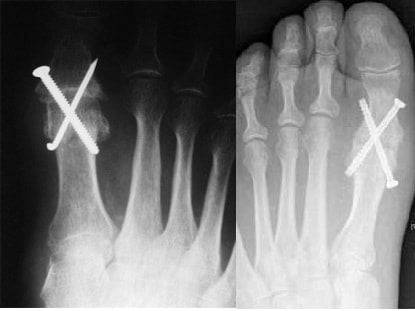

Оперативное лечение может исправить многие патологии связок и сухожилий, связанных с ревматоидным артритом стопы и голеностопного сустава благодаря использованию специальных скоб и бамперов. Однако во многих случаях наиболее успешный хирургический вариант — слияние (артродез). Этот вид операции часто делают на большом пальце, пятке и лодыжке.

При артродезе хрящ удаляется из сустава, а кости закрепляются в нужном положении винтами и пластинами или винтами и стержнем. Хирург может имплантировать костный трансплантат с бедра или другого участка ноги. Кости объединяются, чтобы создать новое здоровое соединение. После операции и реабилитационного периода боли в ноге уходят, функционирование сочленения восстанавливается. Хирургическим способом лечения можно заменить поврежденный голеностопный, коленный и тазобедренный суставы.